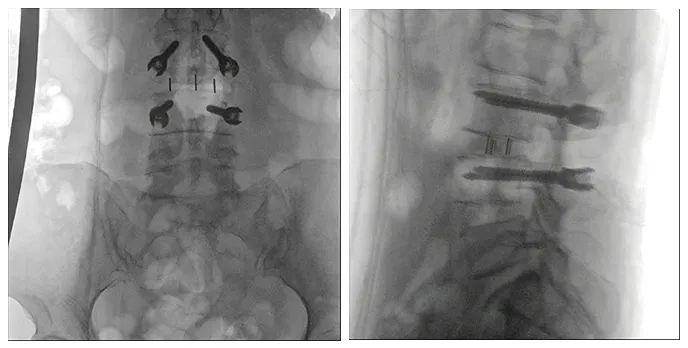

病例二

患者:女性,58歲

術(shù)式:腰骶椎椎體間融合術(shù)

患者一個月前因雙側(cè)下肢疼痛至醫(yī)院就診,診斷為腰椎間盤突出?;颊咦孕兄猎\所就診,予以推拿牽引術(shù),疼痛未明顯緩解,到醫(yī)院進一步治療。影像診斷:L3-4椎間盤突出,椎管變窄(中央型)。

術(shù)前影像

使用普愛醫(yī)療術(shù)中三維導(dǎo)航C臂進行透視,根據(jù)透視影像引導(dǎo)確認責(zé)任間盤、規(guī)劃手術(shù)方案,充分暴露骨組織,并通過專業(yè)器械切除椎板,暴露神經(jīng)及椎管;在C形臂的引導(dǎo)下,確定責(zé)任間盤上下椎體椎弓根位置,制定進針點及進針方向,沿椎弓根方向植入脊柱螺釘進行固定;放入椎間融合器,加固螺釘。最后再進行C形臂透視,確認手術(shù)的完成效果。

手術(shù)效果確認